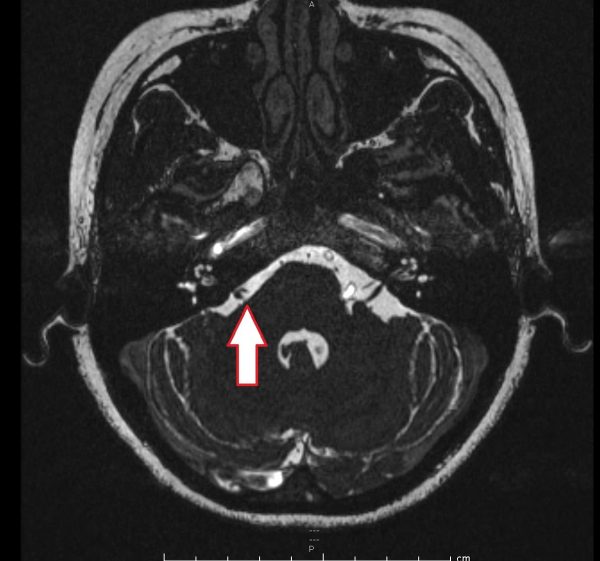

这是一项微创手术,从耳朵后面的头颅上钻开小孔,经过小脑和大脑,找到膨胀弯曲的血管,将之挪开,然后在颜面神经线的出口处放一小块医疗用特氟龙(Teflon),避免神经线受挤压。

为了避免伤及神经,接近6小时的手术全程以颜面神经及听觉神经监控系统严密监测,确保安全。

术后,琦琦恢复良好,6星期后复诊,脸部的抽搐已经平伏了许多,只剩下轻微的颤动,左脸的线条也向上提拉了,两边脸的轮廓显得比较平衡。